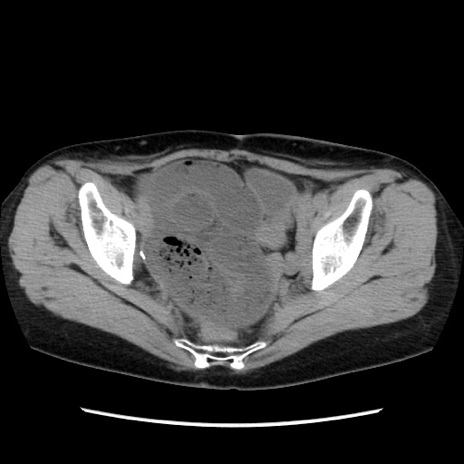

症例32(横断像)

【症例】40歳代 女性

【主訴】上腹部痛、嘔気・嘔吐

【現病歴】約9時間前頃から急に上腹部痛、嘔気、嘔吐が出現。改善しないため救急要請。

【既往歴】子宮頚癌(広汎子宮全摘術、放射線療法)、腸閉塞

【身体所見】腹部:平坦、軟、腸雑音亢進、上腹部を中心に腹部全体に圧痛あり。

【データ】WBC 8400、CRP 0.03